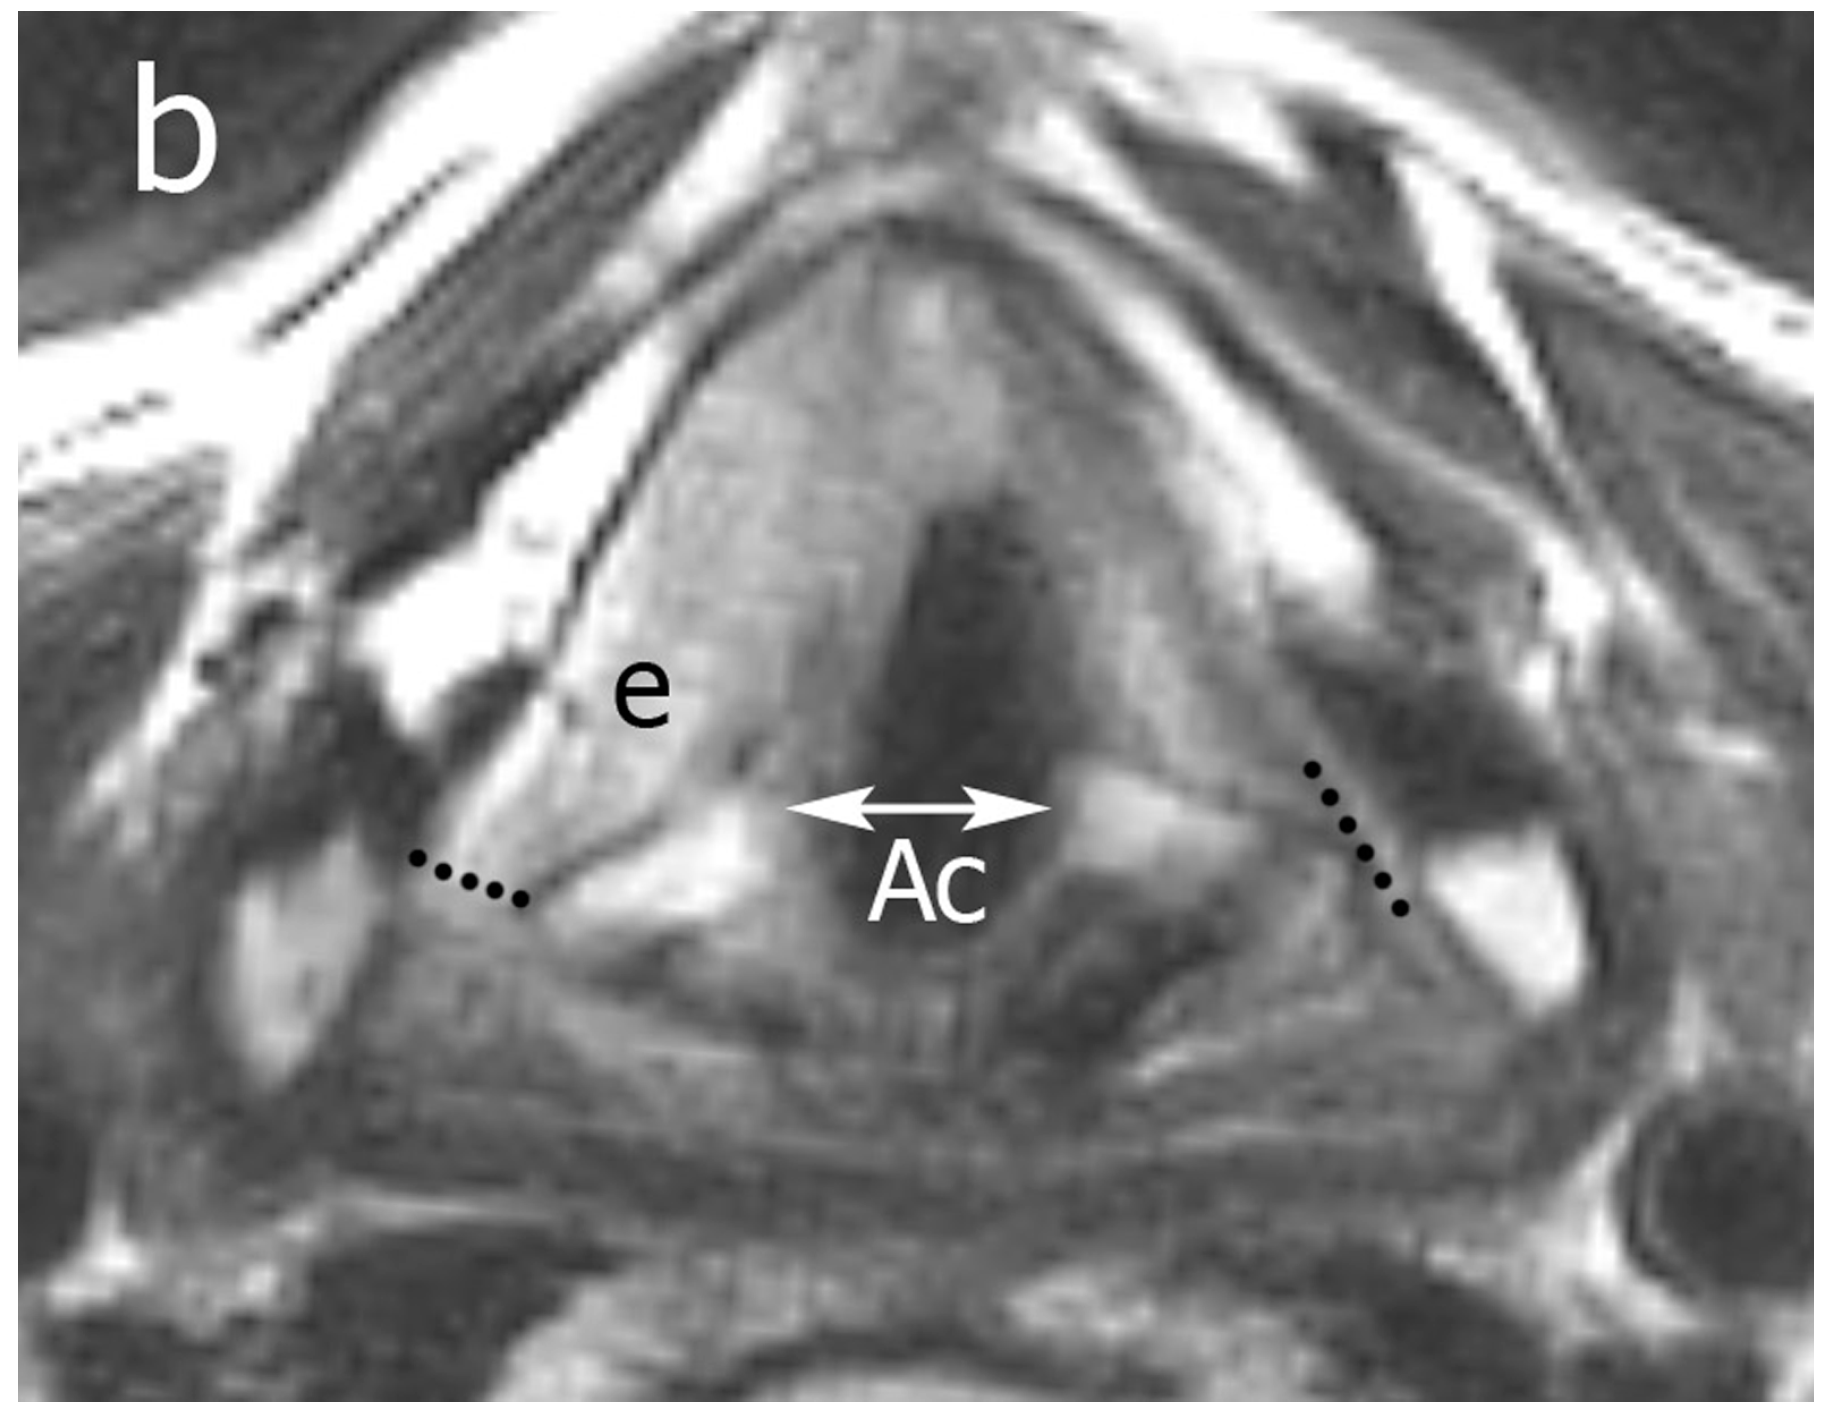

Glottic map subsites and layers of depth. AC anterior commissure Posterior Glottic Diastasis Posterior glottic diastasis (pgd) is an underappreciated etiology of. posterior glottic diastasis (pgd) is an underappreciated etiology of dysphonia in patients with prior airway reconstruction or. dysphonia secondary to posterior glottic aerodynamic incompetence can often be recognizable acoustically, but difficult to. the purpose of this study was to report our clinical experience in the surgical management of. Posterior Glottic Diastasis.